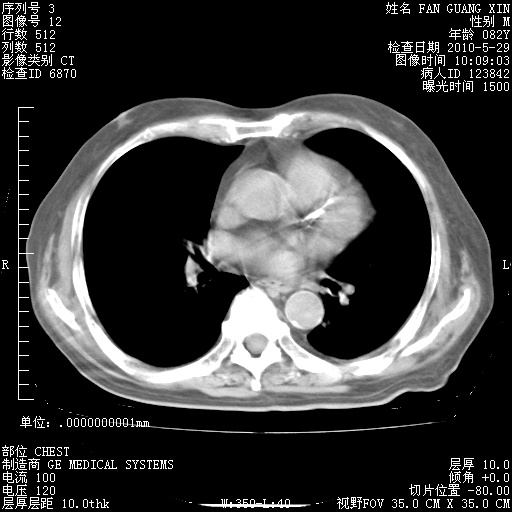

治疗3周后的肺部CT纵隔窗

再治疗10天后的肺部CT

再治疗10天后的肺部CT 纵膈窗

阅读此次胸部CT,肺间质渗出性改变较入院时有吸收。目前从体温、白细胞、中性分叶明显增高,肯定存在细菌感染(发生医院感染哦,若无消化道及泌尿系统等感染的依据,肺部感染可能大)。若你院头孢哌酮舒巴坦钠耐药率较高,同意你的方案,若48小时体温仍高,可考虑使用碳青霉稀类抗菌药物,同时可予超声雾化、注意滴数时加大液体量。白蛋白33.30g/L较低哦,需加强营养等支持治疗。